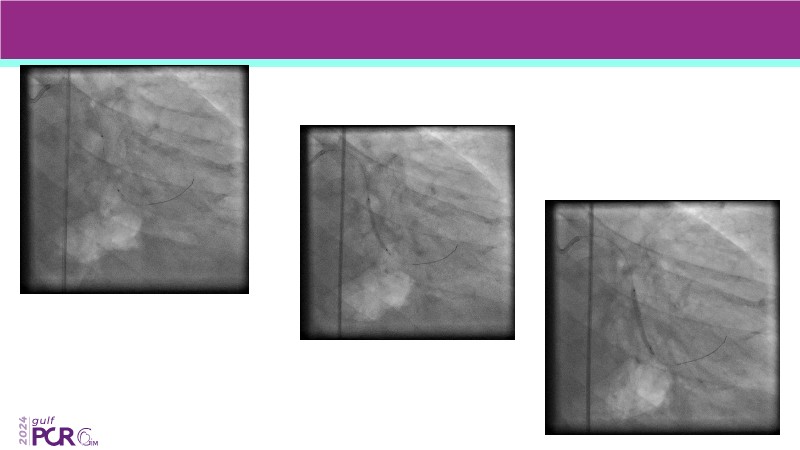

- To discover your next gen complex PCI toolkit with thin strut platforms and dedicated stenting solutions for managing side branch and long diffused lesions

- To achieve goals of metal-free PCI in your patients using drug eluting balloons